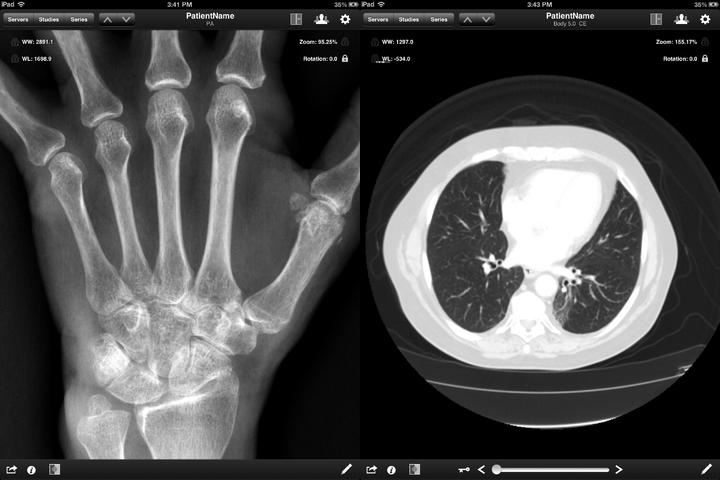

Jack Imaging Medical Image Viewer

2013年,Nephosity公司报道一款用于iPad的APP,MobileCT Viewer获得FDA认证。那时还没有在iTunes App Store发布,原因想改善完善功能,与当时处于测试版的Jack Imaging 融合,现在Jack Imaging已公开发布了。 Jack Imaging同样具有远程诊断影像图片的功能,不用连接工作站的情况下,就能查看CT 、MRI、 X-ray等图像。 Jack Imaging是iPad专用的医疗图像浏览软件,采用了nephosity的专利技术,支持用户互动使用,包括触屏缩放、平移、亮度与对比对调节,呈现高清图片,让图片所有细节一览无余、同样符合HIPAA协议规范,能测量图像距离,并注解图片。